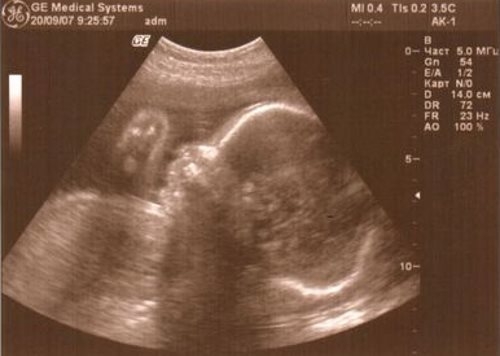

Фото УЗИ на 27 неделе беременности

На данном этапе беременности ультразвуковое исследование не является обязательным и проводится только при наличии определенных показаний. В это время уже можно с уверенностью определить пол будущего ребенка (с вероятностью 100%). В процессе обследования особое внимание уделяется состоянию плаценты, которая должна иметь толщину около 27 мм, а ее степень зрелости должна быть равна нулю.

Специалист анализирует развитие плода, исследует его органы и фиксирует частоту сердцебиения. Если частота превышает 190 ударов в минуту, требуется провести допплерографию сосудов.

Кроме того, врач оценивает размеры плода. В случае выявления недостатка или избытка массы тела, женщине рекомендуется пересмотреть свой рацион питания.